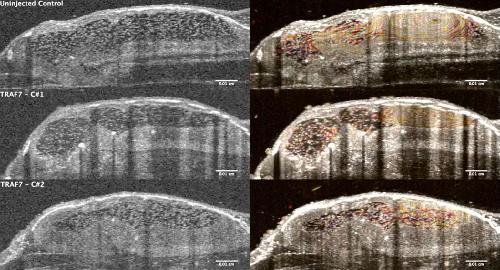

Pleiotropic role of TRAF7 in skull-base meningiomas and congenital heart disease., Mishra-Gorur K, Barak T, Kaulen LD, Henegariu O, Jin SC, Aguilera SM, Yalbir E, Goles G, Nishimura S, Miyagishima D, Djenoune L, Altinok S, Rai DK, Viviano S, Prendergast A, Zerillo C, Ozcan K, Baran B, Sencar L, Goc N, Yarman Y, Ercan-Sencicek AG, Bilguvar K, Lifton RP, Moliterno J, Louvi A, Yuan S, Deniz E, Brueckner M, Gunel M., Proc Natl Acad Sci U S A. April 18, 2023; 120 (16): e2214997120. |